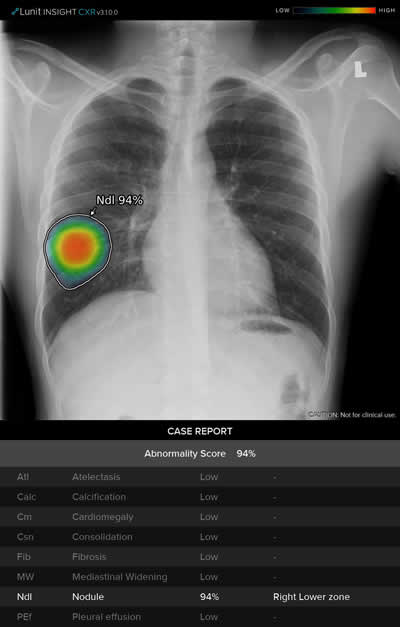

El Sistema Thoracic Care aprovecha el poder de la IA para ayudar a disminuir esta sobrecarga mediante el análisis automático de imágenes, el cual detecta la presencia de hasta ocho resultados radiológicos anormales, incluidos indicios de tuberculosis y neumonía, que pueden ser indicativos de Covid-19. Al leer el informe en los sistemas de archivo y comunicación de imágenes (PACS), los radiólogos pueden encontrar rápidamente el puntaje de anormalidad para cada una de las ocho posibles anomalías, así como una superposición de imágenes y una descripción de ubicación escrita para ayudar a acelerar el diagnóstico y el tratamiento.

Además de detectar la neumonía, este sistema también está diseñado para identificar otras enfermedades como la tuberculosis, atelectasia, calcificación, cardiomegalia, fibrosis, ensanchamiento mediastínico, nódulo pulmonar y derrame pleural.